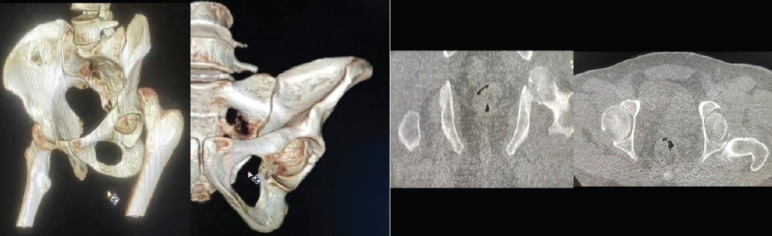

Case report: A 39-year-old male came to casualty with an alleged history of road traffic accident with multiple fractures in bilateral upper limb, multiple rib fractures, and brachial plexus injury. Computed tomography of the pelvis with both hips was done, which showed a fracture of the left femoral head with a proximal fracture fragment found inside the acetabulum with posterior dislocation of the distal part - left femoral head fracture dislocation (Pipkin type I). Closed reduction of the hip joint failed; hence, open reduction using the Kocher-Langenbeck (KL) approach was carried out, head reduced, transfixed with guide wires, and fixed with three CC screws. On the last follow-up at the end of 1 year, the patient has regained full range of motion of the hip. Patient is able to squat, sit cross-legged, and is able to walk unaided.